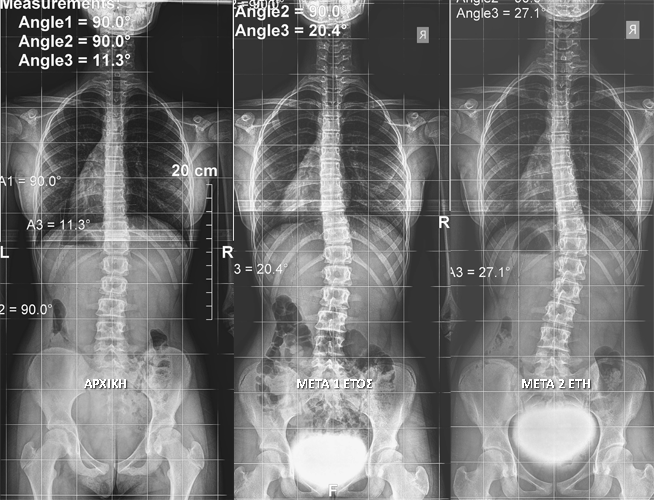

Η παρακολούθηση είναι το πρώτο βήμα σε μια ενεργή προσέγγιση της ιδιοπαθούς σκολίωσης και αποτελείται από κλινικές αξιολογήσεις που πραγματοποιούνται σε τακτά χρονικά διαστήματα, που κυμαίνονται από κάθε 2-3 μήνες έως κάθε 36-60 μήνες ανάλογα με τη μεμονωμένη περίπτωση.

Στο SPONDYLOS προτιμούμε την ανάπτυξη ως μέσο σύγκρισης. Δηλαδή επανεξετάζεται ο ασθενής μετά από αύξηση του ύψους κατά 4-5 εκατοστά.